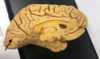

Gyrus/Sulcus Flashcards

(23 cards)